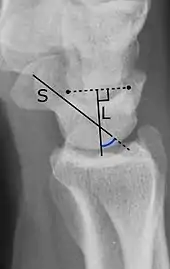

The SL angle is an indicator of dorsal intercalated segment instability deformity (DISI). The SL angle goes between:[1]

- A line through the long axis of the scaphoid bone.

- A line perpendicular to the distal articular surface of the lunate bone.

It should normally be 30°-60°.[1]